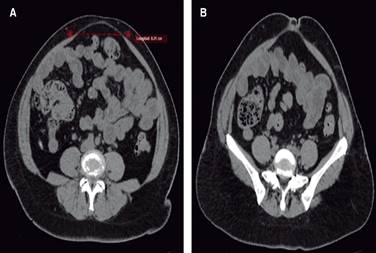

Tras la inspección, se solicita TC de abdomen, la cual se realiza el 03.01.2023, reportando, a nivel supraumbilical, umbilical y justo por debajo de cicatriz umbilical, separación de músculos rectos abdominales de hasta 8.21 cm, fascia abdominal anterior integra, excepto en región umbilical en donde se observa una solución de continuidad de 9.6 mm, con formación de saco herniario de 7.5 × 1.75 mm de contenido epiploico. Se clasifica cómo una diástasis de rectos severa (Figura 2).

Figura 2: Tomografía computarizada simple corte axial. A) Diástasis de rectos abdominales de 8.21 cm. B) Diástasis de los rectos abdominales que se asocia a hernia umbilical.